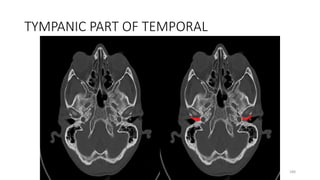

TYMPANIC PART OF TEMPORAL

180